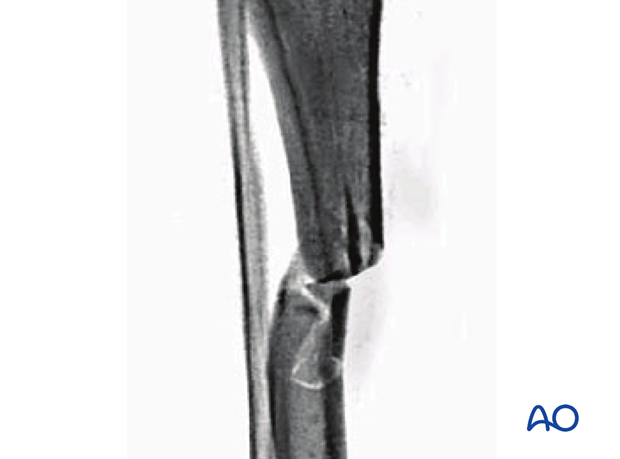

These are classified as AO/OTA 42B3 fractures. These are multifragmentary diaphyseal fractures of the tibia. Once the fracture is reduced, there is contact between the proximal and distal fragments.

The wedge component of this fracture can be fractured in two or more fragments.

These fractures are caused by high-energy impact.

This x-ray reveals a fragmentary wedge fracture of the tibia.